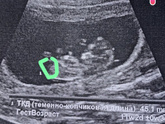

18 июля 2022 13:43 Сходила на узи ??? все отлично , срок по последним месячным 12 недель , а по узи 11.2 недели узист сказал это не страшно , срок на 4 февраля ИншАллах ? Кто там с таким срокам ? Давайте дружить ☺️❤️